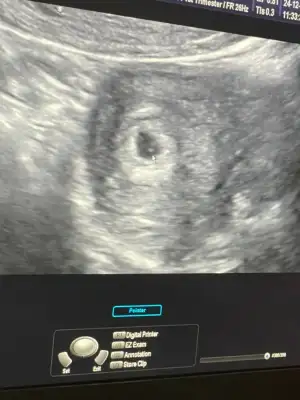

Eveet işte burda yolk gözüktü🥳